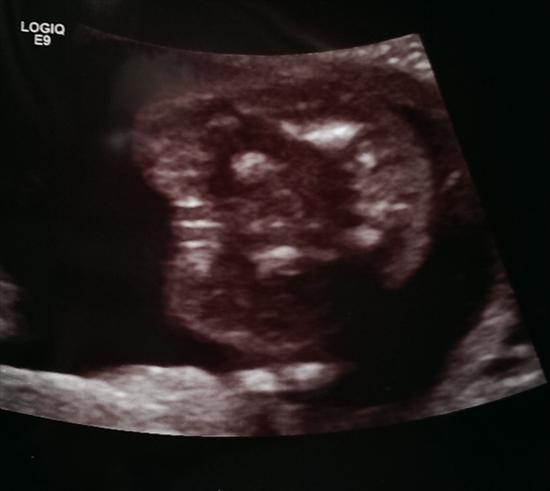

Potty shot is 20w2d

wow that is perfectly a girl.... it would be nice for all the girl swayers to get a potty shot just as perfect as that one!

Congrats! I thought your nub was girly :)